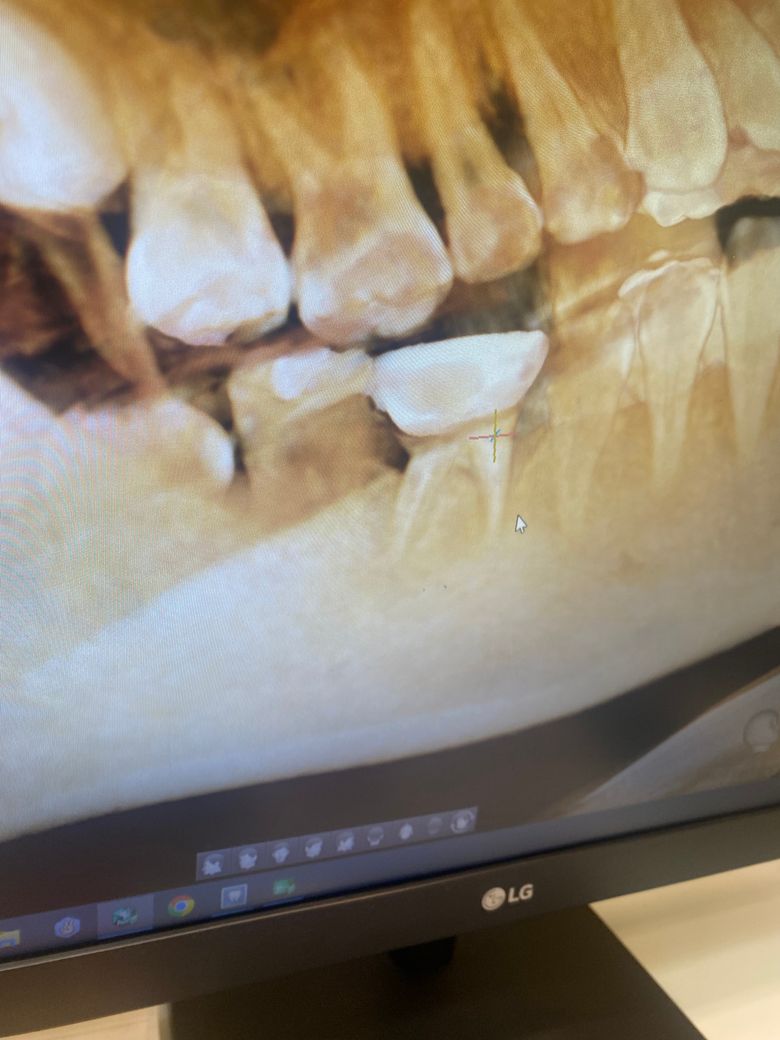

선생님들... 제 어금니 잇몸상태 어떤가요..?

크라운 한 잇몸을 누르니 고름이 나와

치과를 다녀왔습니다..

엑스레이로 염증을 확인할 수도 있나요?

하나는 ct인데 상태 마니 안 좋은가요......?ㅠㅠ

사진으로만 봤을 경우에는 뒤쪽 뿌리 부위에 파절이 된것으로 보입니다.

파절된 부위에 이물질이 들어가게 되면 염증이 생길수 있습니다. 뿌리가 파절이 되었을 경우에는 치아를 뽑아야 하는 상황이 생길수도 있습니다.

엑스레이상으로 치아 뿌리끝 염증이 잡힌 것이 보이긴 합니다만 전후 상황이 없기 때문에 정확한 건 파악이 어렵습니다.